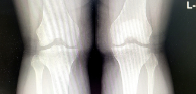

슬개골은 대퇴골과 종아리뼈 사이에 위치한 삼각형 모양의 큰 뼈로 대퇴골과 함께 무릎 관절을 구성합니다. 슬개골은 대퇴골에 연결된 근육과 인대에 의해 위치가 고정되어 있으며, 무릎 관절에서 일어나는 움직임에 중요한 역할을 합니다. 슬개골의 이상 발생 시 무릎 통증, 팽만, 무릎이 튀어오르는 증상 등이 발생할 수 있습니다.

슬개골 연골연화증은 슬개골과 대퇴골 사이에 위치한 슬개골연골이 변성되어 파손되거나, 연화되는 질환입니다. 대개 중년 이상의 여성에서 발생하며, 골다공증, 슬개골 이상운동, 유전적 요인 등이 원인으로 작용합니다. 증상으로는 슬개골 통증, 불안정성, 퇴행성 변화 등이 나타납니다. 진단은 X선, MRI, 초음파 등을 이용하여 확인할 수 있으며, 치료는 보존적 치료(약물 치료, 근력강화 운동 등)와 수술적 치료(슬개골 전방 이동술, 전·후방 상처 수술 등)으로 이루어집니다. 빠른 진단과 치료가 필요하며, 치료를 받지 않으면 슬개골 골관절염, 연골 파괴 등 심각한 합병증이 발생할 수 있습니다.